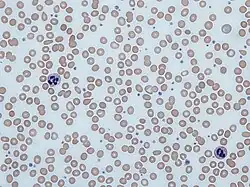

Platelet storage pool deficiency is a family of clotting disorders characterized by deficient granules in platelets. Individuals with these disorders have too few or abnormally functioning alpha granules, delta granules, or both alpha and delta granules and are therefore unable to form effective clots, which leads to prolonged bleeding.[3][4] Platelet storage pool deficiency can be acquired or inherited.[3]